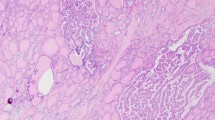

Thyroid glands from the four PDS patients were diagnosed as nodular and diffuse hyperplasia, regardless of their functional thyroid status. Multiple follicular adenomas, as well as even a subcentimeter papillary thyroid carcinoma, were observed in two of the patients (Table 1, Fig. 1A–C). The hyperplastic thyroid tissue showed areas with different follicular patterns, such as normal sized thyroid follicles (Fig. 1D), microfollicles (Fig. 1E), follicles with papillary infoldings within the lumen or “papillary follicles,” some exhibiting tall columnar cells and empty colloid in the lumen (Fig. 1F). In those areas, scattered cells with nuclear atypia and hyperchromasia were observed. Oncocytic changes of follicular cells were also seen in different follicular patterns, either as solitary or grouped cells.

Histopathological characteristics of thyroid tissue in PDS patients stained with hematoxylin–eosin. Panoramic visions of thyroid samples in which diagnosis of nodular and diffuse thyroid hyperplasia (PDS1; A); diffuse thyroid hyperplasia with a highly cellular follicular nodule (HCFN) (black asterisk) (PDS2; B); and follicular adenoma (blue asterisk) (PDS3; C) were made. In amplifications of those thyroid tissues, different histologic patterns can be distinguished: D normal thyroid follicles; E microfollicles; F papillary follicles; G HCFN with microfollicular pattern and interstitial fibrosis; H HCFN with spindle cell features, and finally, I follicular adenoma exhibiting a trabecular pattern. Scale bars: 70 µm (A–C), 25 µm (G–L)

Moreover, another common alteration consisted of markedly well-defined nodules with a dense cellular growth pattern (HCFNs). HCFN areas exhibited a variety of architectural appearances, which were frequently surrounded by diffuse hyperplastic thyroid tissue (Fig. 1B, black asterisk). In some cases, HCFNs presented a microfollicular pattern with abundant fibrosis and hyalinization of the stroma (Fig. 1G); in other cases, HCFNs exhibited spindle cell features (Fig. 1H). Multiple follicular adenomas were also diagnosed (Fig. 1C, blue asterisk), according to either a solid, microfollicular, or trabecular growth pattern (Fig. 1I). Although in some areas follicles with papillary infoldings were found, no true follicular thyroid adenomas with papillary architecture were observed. Additionally, extensive zones with hemorrhage and destroyed follicles were identified along different thyroid sections, altogether with abundant fibrosis. Finally, no C-cell hyperplasia was detected in our series, either in routine examination of the surgical specimens or by immunostaining of calcitonin.